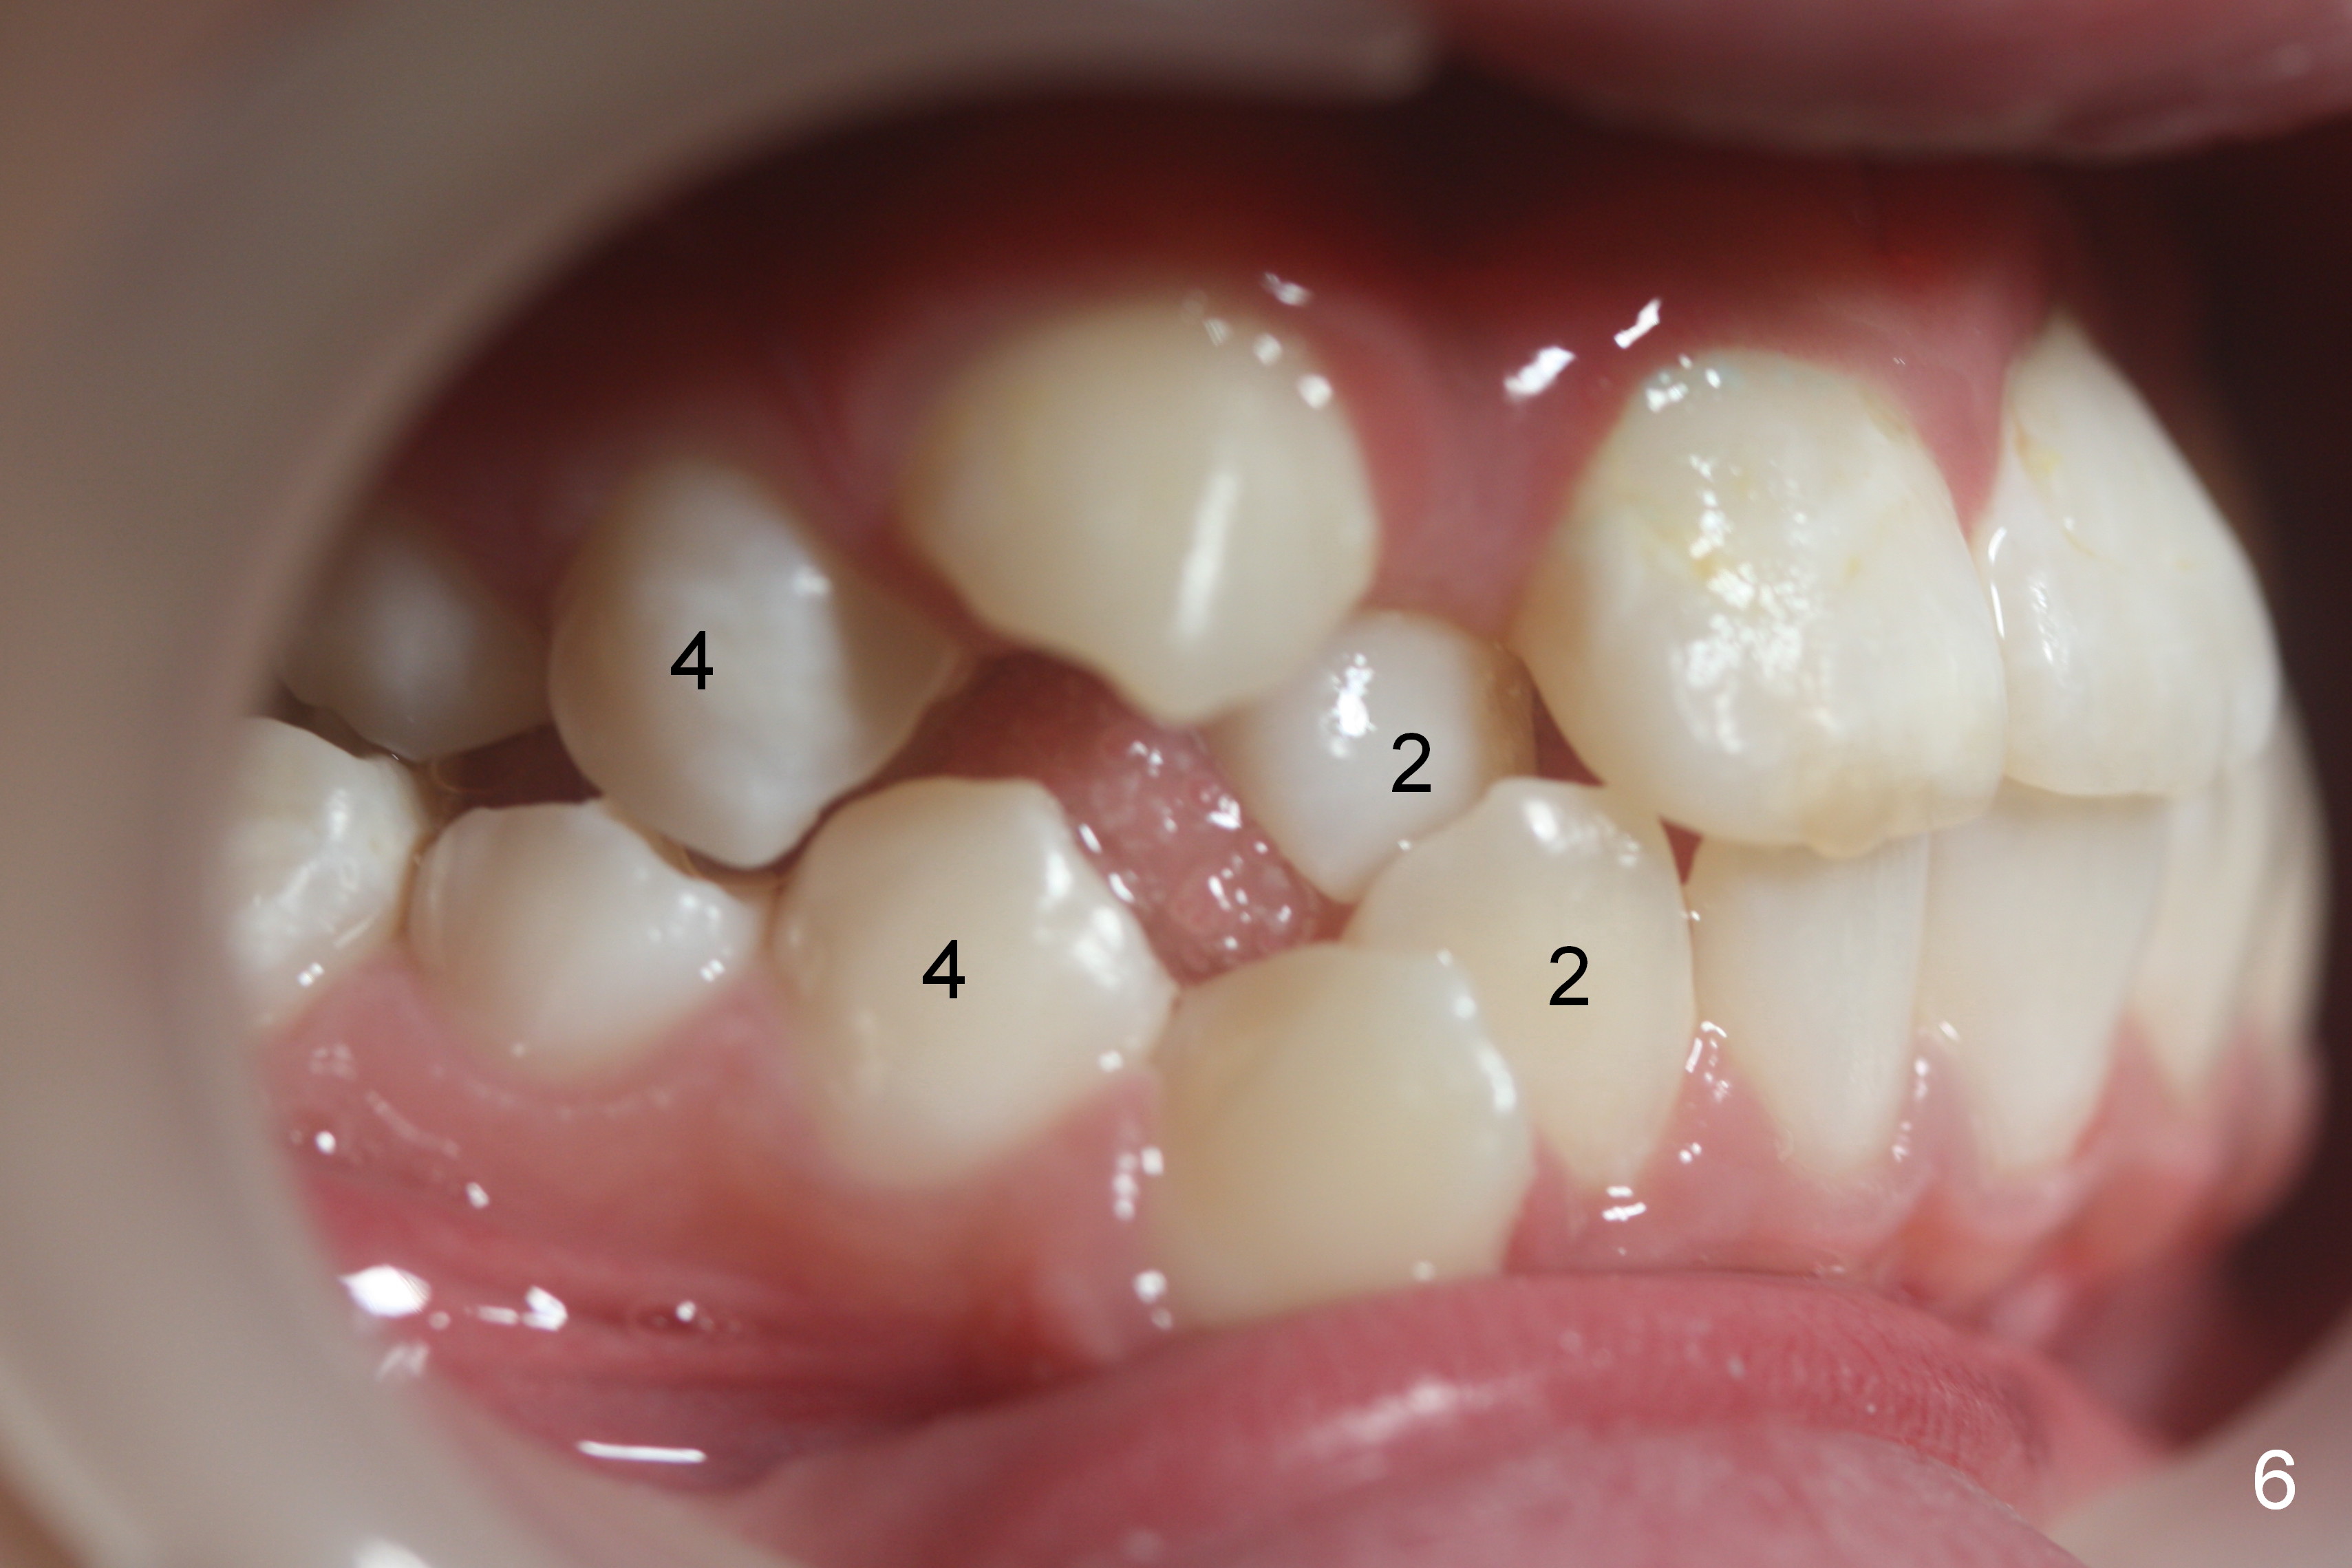

A 10-year-old girl with history of hyper-thyroidism has severe Class I malocclusion. She is ready for treatment. There is mild lip strain (suggesting anterior tooth protrusion, Fig.1,3). The facial and dental midlines coincide (Fig.2). Severe crowding is evident. Extraction orthodontics is indicated, either next to the most crowded areas (UR, LR4, Fig.6) or impacted ones (UL, LL5, Fig.10,11 (mirror view)).

No brackets are placed at UR, UL, and LR 2 (blocked out, Fig.6,8) initially. Open coil spring is placed to gain the space with .018 stainless steel wires. When the space is almost achieved, sling shot is installed for labialization. When the space has been completely achieved and the lateral is almost in the normal position, place the bracket upside down.

The right canines are blocked (Fig.6,9). Use an elastic between them as early as possible to facilitate eruption, which is not done immediately post banding and extraction of R4s (Fig.12 (.014' niti wires)).